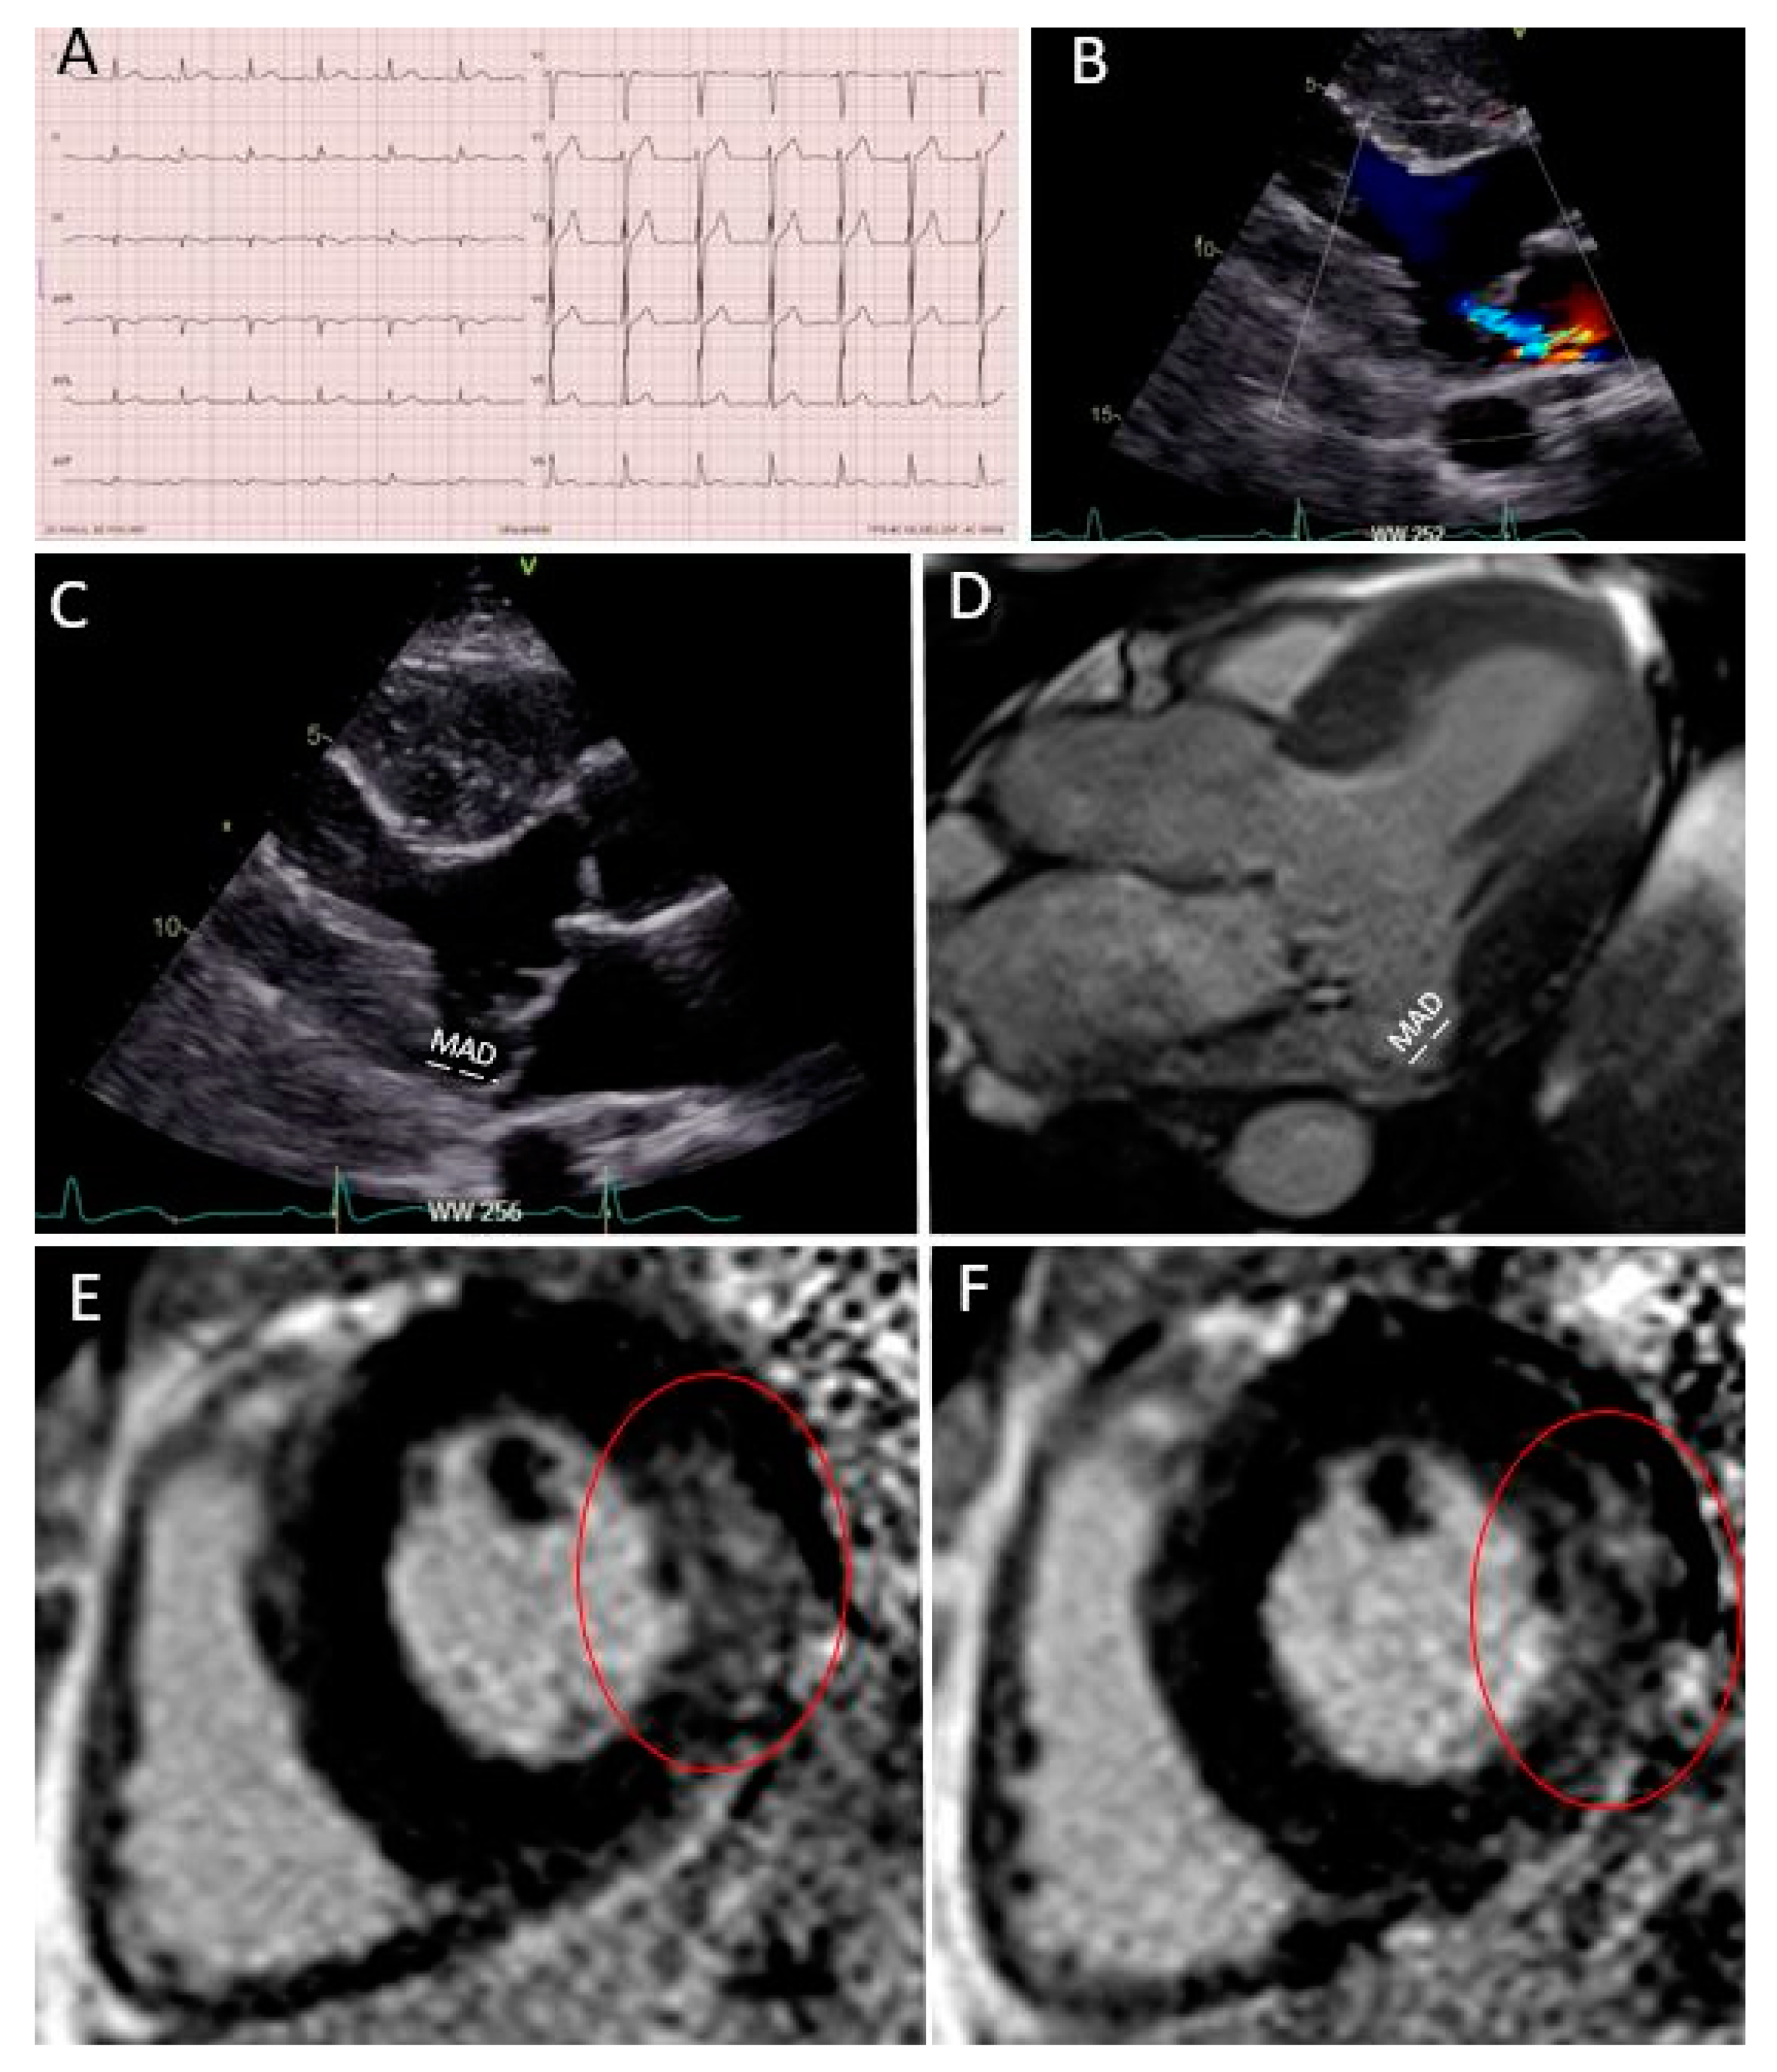

Figure 1.

“Red Flags” in echocardiography and cardiac magnetic resonance imaging (CMR): (A) MAD measured in a parasternal long-axis view (transthoracic echocardiography); (B) “Pickelhaube sign” during transthoracic echocardiography; (C) MAD measured in a steady-state free precession three-chamber view during CMR; T1 mapping native (D) and after gadolinium injection (E); macroscopic fibrosis in the inferior basal wall highlighted with red arrows in a free-breathing LGE sequence (F). ECV, extracellular volume; LGE, late gadolinium enhancement; MAD, mitro-annular disjunction; PM, papillary muscle, GLS: Global Longitudinal Strain.

Case 1: Primary prevention ICD implantation after multi-modality imaging work-up. (A) Patient’s ECG; (B) moderate mitral regurgitation during color Doppler transthoracic echocardiography; (C) bileaflet prolapse with MAD (in white); (D) “Pickelhaube sign” during transthoracic echocardiography; (E) MAD measured in a steady-state free precession three-chamber view during CMR; (F,G) a large zone of fibrosis in the basal inferior wall in LGE sequences (red circle).

A 22 year-old female patient was known for mitral valve prolapse since infancy. Her baseline ECG showed negative T waves in the infero-lateral leads (Figure 2A) and mitral regurgitation during echocardiography was moderate (Figure 2B). She was symptomatic for mild palpitations. However, several “red flags” were present (female sex and baseline ECG), as well as a bileaflet prolapse with MAD (Figure 2C) and a Pickelhaube sign (Figure 2D) during transthoracic echocardiography. Considering the patient’s symptoms and the presence of “red flags” in the baseline assessment, she underwent a 24 ECG Holter examination, which showed the presence of several ventricular extrasystoles (>20,000), and the CMR study confirmed the presence of MAD (Figure 2E). In addition, a large zone of fibrosis in the basal inferior wall was visible (Figure 2F,G red circle). The extracellular volume was high in all basal left ventricular segments. In this case, with several “red flags,” an invasive electrophysiology study (EPS) study was undertaken to more precisely stratify the arrhythmic risk. The EPS showed the induction of ventricular tachycardia and even ventricular fibrillation. For this reason, a subcutaneous implantable cardioverter defibrillator (ICD) for primary prevention was finally implanted. The patient was also treated with 2.5 mg of bisoprolol, and a reduction in ventricular arrhythmias was documented at follow-up.

Case 2: Secondary prevention ICD implantation after cardiac arrest and multi-modality imaging work-up. (A) Patient’s ECG; (B) moderate mitral regurgitation during color Doppler transthoracic echocardiography; (C) bileaflet prolapse with MAD (in white); (D) MAD measured in a steady-state free precession three-chamber view during CMR; (E,F) a large zone of fibrosis in the basal and mid-lateral wall in LGE sequences (red circle).

A 40 year-old man was known for mitral valve prolapse since adolescence and was periodically followed by a cardiologist. Baseline ECG was not remarkable (Figure 3A), mitral regurgitation was moderate during echocardiography (Figure 3B), and the patient was asymptomatic in his daily life. However, he presented several “red flags” during echocardiography, in particular, the presence of a bileaflet mitral valve prolapse with MAD (Figure 3C). Then, the patient suffered a cardiac arrest on ventricular fibrillation during jogging and he was admitted to the emergency room. Coronary angiography was normal. Moderate mitral regurgitation was confirmed upon urgent echocardiography. During continuous ECG monitoring in the intensive care unit, several ventricular extrasystoles were noticed. CMR was then performed, confirming the presence of MAD (Figure 3D) and demonstrating a large zone of fibrosis in the basal inferior wall (Figure 3E,F, red circle). The extracellular volume determined by T1 mapping was high in all basal left ventricular segments. The patient then underwent an EPS, which showed the induction of ventricular tachycardia and ventricular fibrillation. A subcutaneous ICD was finally implanted as a secondary prevention measure, and treatment with 80 mg/day of nadolol was started. No arrhythmic events were present at the one-year follow-up.